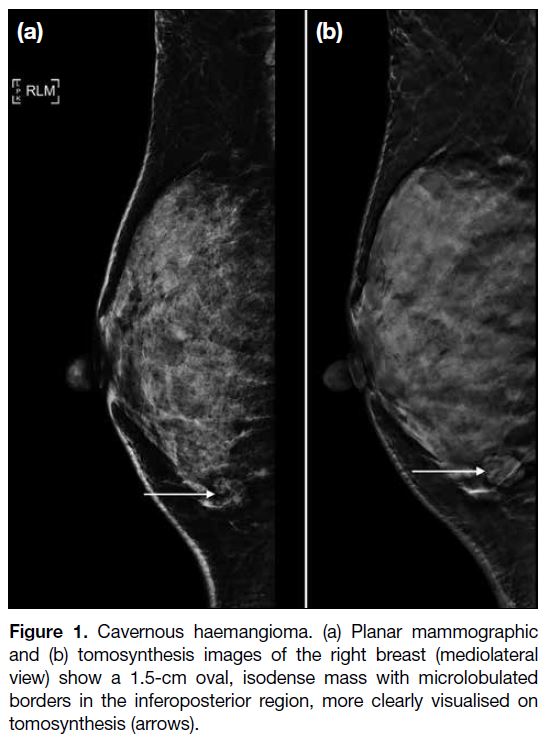

On mammography, haemangiomas are usually equal

dense to the breast tissue, and oval in shape with

circumscribed or microlobulated margins (Figure 1).[2] Intralesional microcalcifications may be found

occasionally[2], which may lead to the need for imaging

surveillance or core biopsy.

Figure 1. Cavernous haemangioma. (a) Planar mammographic

and (b) tomosynthesis images of the right breast (mediolateral

view) show a 1.5-cm oval, isodense mass with microlobulated

borders in the inferoposterior region, more clearly visualised on

tomosynthesis (arrows).